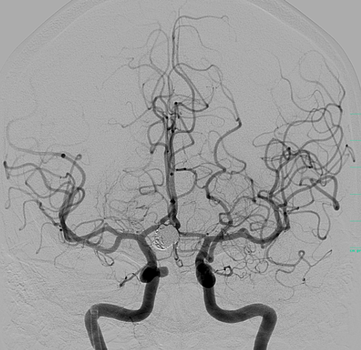

Die Neuroradiologie beschäftigt sich mit der Diagnostik und Therapie von Erkrankungen des Gehirns, des Rückenmarks und der dazugehörigen Gefäße. Wir bieten sämtliche diagnostische und endovaskuläre Verfahren an. Ein besonderer Schwerpunkt liegt auf der interventionellen Behandlung von Gefäßerkrankungen, wie beispielsweise Aneurysmen, Angiomen, duralen AV-Fisteln, angeborenen Gefäßmissbildungen, Engstellen der hirnversorgenden Schlagadern oder der mechanischen Wiedereröffnung von Gefäßen beim akuten Schlaganfall.